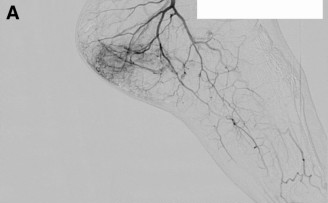

Plantar Fasciitis Embolization (PFE)

PFE (also described as transarterial embolization/microembolization for plantar fasciitis) is an image-guided outpatient procedure intended to reduce abnormal “pain blood vessels” (neovessels) associated with chronic plantar fascia irritation.

Before

After